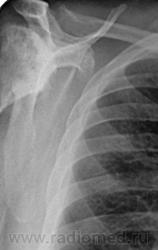

Снимки плечевых суставов.

Foto010.jpgFoto011.jpgFoto012.jpgFoto013.jpg

Уважаемый Александр, приходиться признать, что на цифровой рентгенограмме легких изменения плечевых суставов видны лучше, чем на "обрезаных" и недоэкспонированых снимках суставов. По имеющимся данным могу только сказать, что деф. артроз с кистовидной перестройкой структуры есть. Под хрящевой опухолью (возможно - хондросаркома) левой лопатки я имела в виду тень, отмеченую красными стрелками, которая в поле снимка не вошла. Моя вина - в силу специфики работы такие узкоформатные снимки давно были вредными, т.к. очень часто патология остается за пределами снимка. Остается рекомендовать рентгенография левой лопатки в прямой передне-задней и косой проекциях, а лучше - КТ...